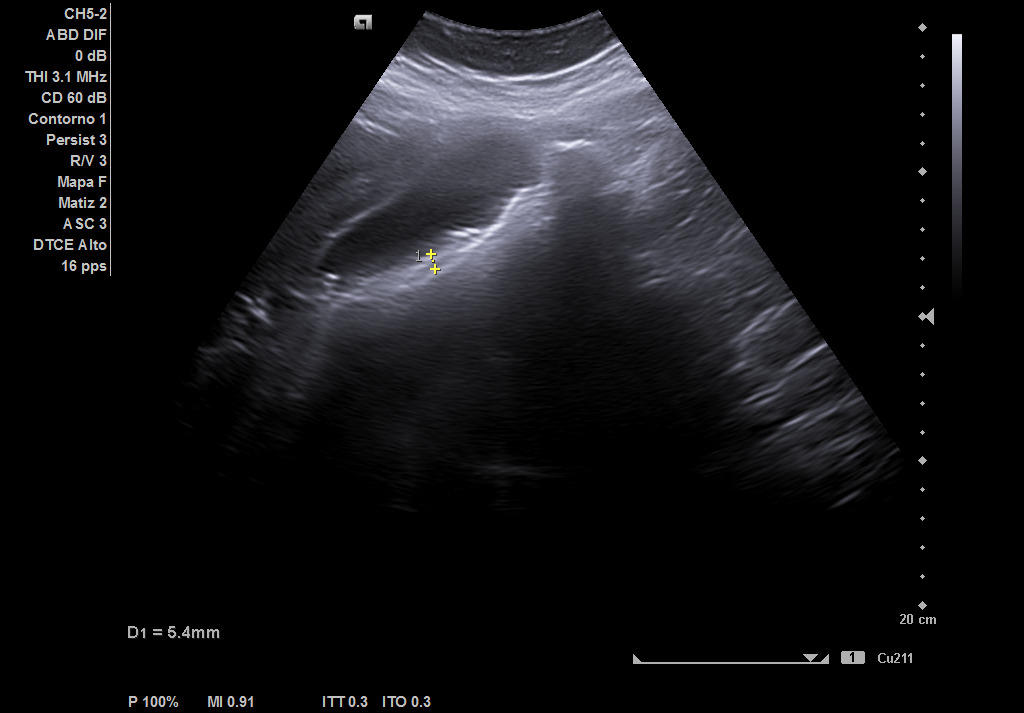

Hallazgos ecográficos

Hígado de tamaño, forma y ecoestructura conservadas, con parénquima homogéneo. Vena porta de calibre conservado. Colédoco dilatado, de 8,8 mm. Vesícula biliar de paredes gruesas y edematizadas (5,4 mm) en cara posterior, con contenido ecogénico y 2 microlitiasis en su infundíbulo.